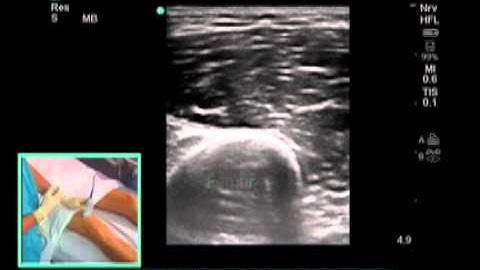

How To: Ultrasound Guided Saphenous Nerve Block 3D Video